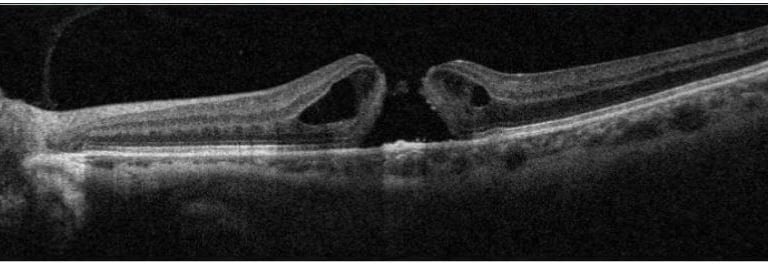

Degeneração Macular Relacionada a Idade (DMRI)